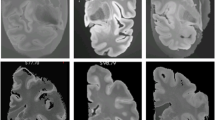

The herein employed technique to generate multi-sequence average templates from 990 individual MRI scans is referred to as Minimum deformation averaging (MDA)25. MDA exploits the information contained within inter-individual variations to generate an unbiased, high-resolution, high-contrast population average. Through iterative model building, single-subject data is repeatedly aligned to capture the average morphology of the population used in model generation, yielding a final template of superior imaging quality. The MDA pipeline applied in the generation of our multimodal templates is featured in Fig. 1 and described as follows:

Workflow for the generation of the multimodal high-resolution MRI template. (a) 1000 minimally preprocessed T1-weighted (T1w) and T2-weighted (T2w) MRI scans were drawn from the HCP S1200 subject release. Incomplete and corrupted imaging data was excluded during preprocessing yielding 990 scans that were ultimately selected for template generation. Following preprocessing, the antsMultivariateTemplate builder was applied to the scans to perform one round of affine and three rounds of iterative non-linear registration. This process yielded a high-contrast, high-resolution MRI template of great anatomical detail (voxel size: 0.25 × 0.25 × 0.25 mm). Based on this dataset, a second, template was generated (voxel size: 0.5 × 0.5 × 0.5 mm). (b) Image resolution and contrast across differently sized populations. Representative axial and coronal sections of processed T1w (top) and T2w (bottom) MRI scans featuring the increase in tissue contrast during registration of differently sized populations (one, 50, 100 and 990 subjects). The complete MDA pipeline consisting of one round of affine and three rounds of non-linear registration had been applied to all populations. The resulting high tissue contrast in the final templates facilitated hypothalamic segmentation and allowed visualization of tissue boundaries that would have otherwise not been delimitable. MDA, minimum deformation averaging.

Following preprocessing, the antsMultivariateTemplate builder (https://github.com/ANTsX/ANTs/blob/master/Scripts/antsMultivariateTemplateConstruction2.sh) was applied to the imaging dataset to generate the group averages. This entailed the use of a hierarchical image registration algorithm that applied a total of four rounds of registration to the imaging data-set in a stepwise manner. All steps were performed independently for the T1- and T2-weighted scans. During the first step, a MNI152 NLIN 2009b template (voxel size: 0.25 × 0.25 × 0.25 mm) was used as the initial target to perform an affine registration step scaling the 990 individual scans to MNI space29. In the same instance, the individual subject scans were upsampled to the target resolution using B-spline; the spatial information contained within the scans, however, remained unchanged. Subsequently, three rounds of non-linear registration were performed. During each round of non-linear registration, an average was generated from the brains registered in the previous round and that average was then used as the target for the subsequent registration. Each iteration consequently produced a more detailed average. The resolution and contrast of each subsequent average were qualitatively superior to the previous step (Fig. 1). The final template yielded a high-resolution, high-contrast dataset of enhanced anatomical detail (voxel size: 0.25 × 0.25 × 0.25 mm). Although the spatial resolution of the original subject scans (0.7mm3) would have potentially have allowed us to generate a final template of even higher resolution, a voxel size of 0.25 mm isotropic resolution was deemed sufficient as further increases in resolution would have yielded considerably longer processing times and higher memory demand. In addition, voxel resolutions beyond 0.25 × 0.25 × 0.25 mm would find little application in existing MRI techniques. A second template (voxel size: 0.5 × 0.5 × 0.5 mm) was generated by downsampling the high-resolution template. This template may be used on computers with reduced processing power or for segmentations requiring less anatomical detail.